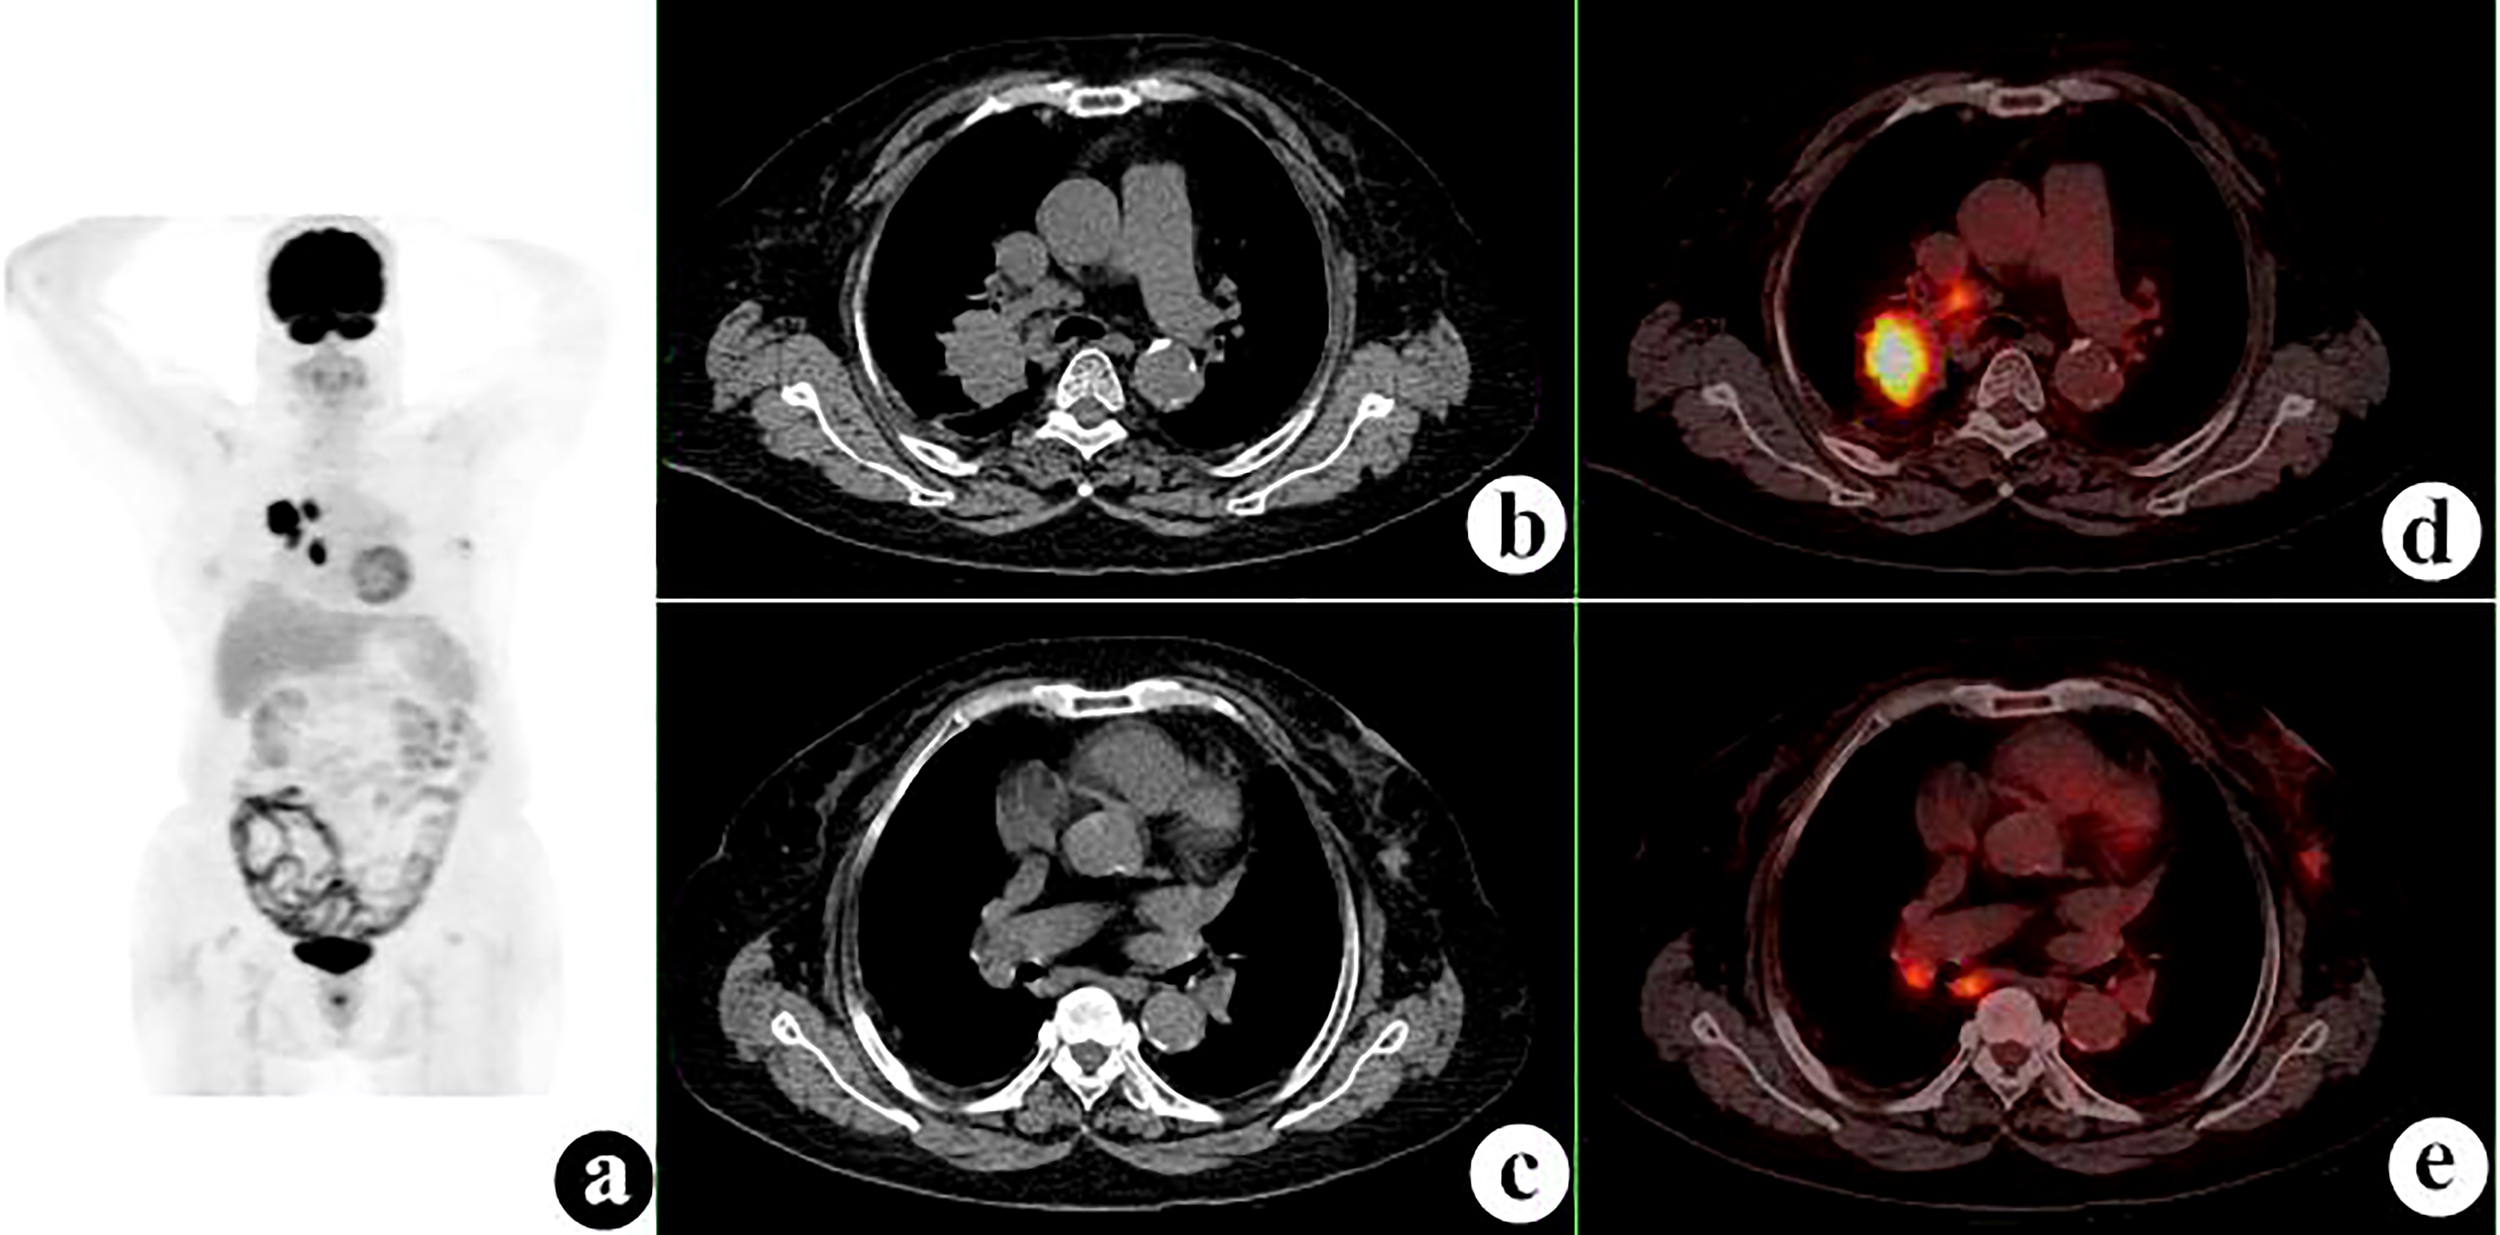

Figure 2 18F-fluorodeoxyglucose positron emission tomography/computed tomography (18F-FDG PET/CT) of a 54-year-old man with lung squamous cell carcinoma and renal small cell carcinoma. PET/CT demonstrated a 52 × 47-mm mass with a maximum standardized uptake value (SUVmax) of 15.5 in the left lower lung and a 30 × 30-mm nodule with SUVmax of 1.1 (white arrows) in the right kidney. Several hilar and mediastinal lymph nodes with different FDG uptake levels were proven to be hyperplasia. (A) PET maximum intensity projection (MIP). (B, C) Axial CT. (D, E) Fusion images.

FIGURE 3

The 74 tumors had an average SUVmax of 12.3 ± 7.9 (range = 0.9–41.7). The primary tumors missed by PET/CT were retrieved and the SUVmax recalculated according to the confirmed site. The average SUVmax ratio, ΔSUVmax, and the DISUVmax of SMPMNs were 4.4 ± 6.9 (range = 0.3–26.7), 7.2 ± 7.6 (range = 0.0–34.0), and 50.3% ± 29.3% (range = 0.0%–96.3%), respectively. The ΔSUVmax values were ≥10.0 in 13 (35.1%) cases (Figure 2), 5.0 ≤ ΔSUVmax< 10.0 in 8 (21.6%) cases (Figure 3), and<5 in 16 (43.2%) cases (Figure 4).